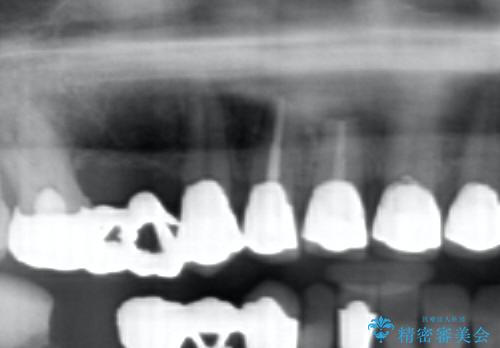

視診・X線写真検査より根尖性歯周炎が認められ再治療が必要な状態です。

再根管治療を行うべくクラウン除去を行ったところ、右上側切歯に保存不可能な垂直性の破折が認められたため抜去が必要になりました。

即切歯の抜歯を行う場合犬歯を含めたブリッジによる補綴計画を立てることが多いですが、今回は犬歯から大臼歯にかかる大きなブリッジが既に装着されていたため予算とご希望を相談し前歯のみの延長ブリッジ補綴で治療を行っていくこととしました。